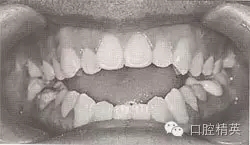

開頜畸形是上下牙弓及頜骨在垂直方向上的發(fā)育異常,其臨床表現(xiàn)是上下頜部分牙在正中頜位及下頜功能運(yùn)動(dòng)時(shí)在垂直方向上無頜接觸(圖9-37),嚴(yán)重者只有個(gè)別后牙有接觸。其形成機(jī)制為前段牙、牙槽或頜骨高度發(fā)育不足,后段牙、牙槽或頜骨高度發(fā)育過度,或兩者兼有。有學(xué)者通過三維頭影測(cè)量技術(shù)對(duì)恒牙早期前牙開頜患者進(jìn)行測(cè)量研究后得出,開頜不僅為高度的不調(diào)畸形,而且是長二寬、高三向的不調(diào)畸形,開頜患者面部寬度顯著減小,上下牙弓明顯狹窄。開頜畸形可發(fā)生在乳牙列、混合牙列和恒牙列,發(fā)生在乳牙列和混合牙列期的開頜畸形的矯治在預(yù)防性矯治章節(jié)中已述及,這里重點(diǎn)介紹恒牙列開頜畸形的矯治。

圖9-37 前牙開頜(牙齒有縫)